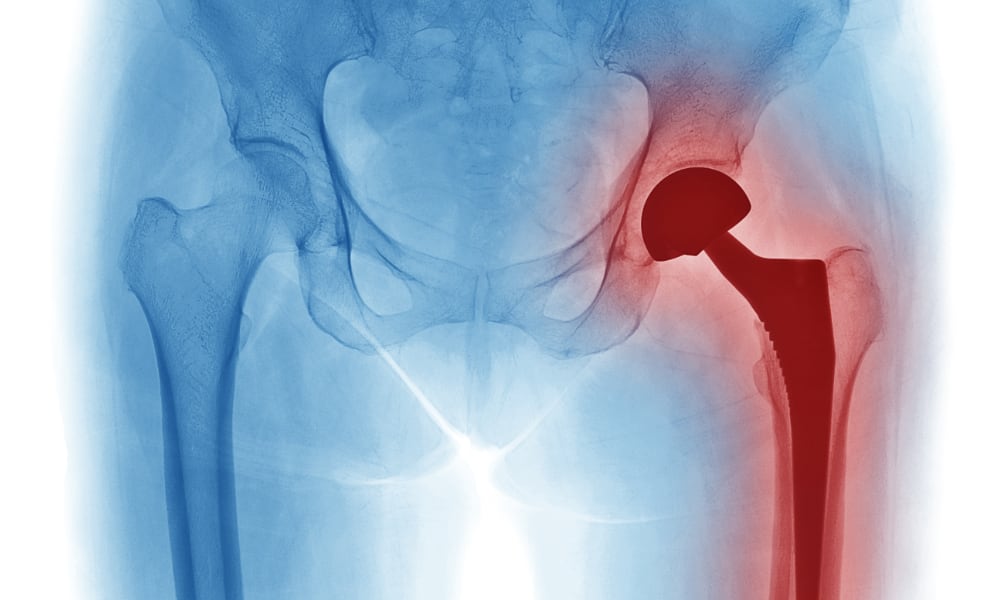

Protez Enfeksiyonları

Protez Enfeksiyonu Nedir? Primer Osteoartrit, Posttravmatik osteoartrit, Romatoid artrit, Avasküle nekroz vb sebeplerle diz ya da kalça protezi yapılmış hastalarda, erken (ilk 1-3 ay) veya geç (3 aydan sonra dönemde protezin yerleştirildiği eklemde septik artrit...